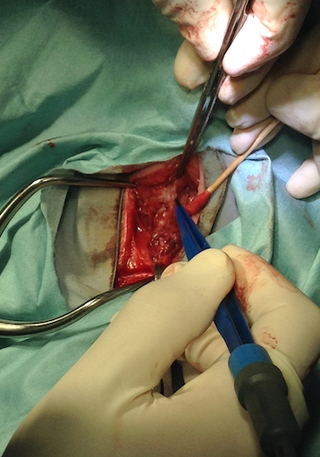

前立腺全切除術 Total Prostatectomy

前立腺全摘出術

前立腺が腫瘍に侵されたケース。

恥骨切除後、骨盤腔内にアプローチ、膀胱と尿道吻合術を実施する。術後に化学療法を併用。